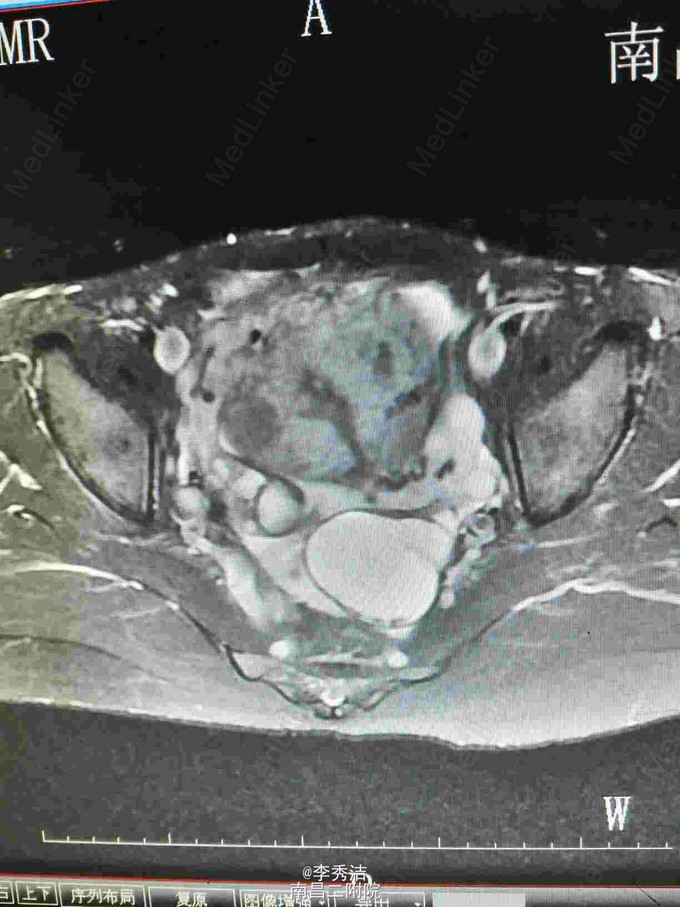

妇科检查:子宫孕9月大小,无压痛,活动。彩超示:子宫体积明显增大,内部呈蜂窝状考虑子宫肌瘤癌变,双侧附件区显示不清。腹部ct示:盆腹腔巨大肿块,子宫及双侧附件显示不清。

行剖腹探查术,术中见子宫血管显露,子宫底部触及一大小约35*30*12cm肌瘤样囊性包块,占据盆腹腔大部分,质软,表面光滑,充满手术野,包块与盆腔后壁肠系膜膜性粘连,右侧卵巢见一直径约5cm囊性包块,表面光滑。松解粘连后,行子宫肌瘤剔除术+右侧卵巢囊肿剔除术,剔除肌瘤16Kg。术中冰冻切片示:(子宫)初步考虑平滑肌瘤伴出血、变性。右侧卵巢良性囊性病变。诊断为1.子宫肌瘤变性,2.右侧卵巢囊肿。